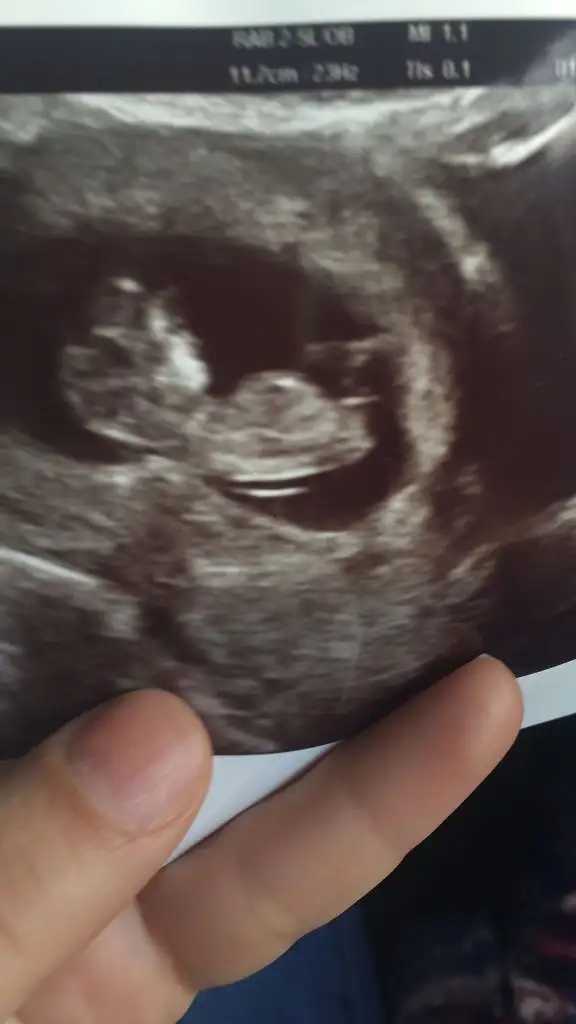

Merhaba daha öncede sormuştum belli değil demiştiniz şimdi 14 haftalık doktor yüzde 50 kız dedi sizce ne

45,2 KB · Görüntüleme: 74